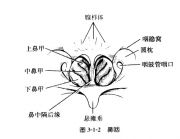

| 2021年7月26日 (一) 20:03 | 咽扁桃体.jpg (文件) |  |

30 KB | Uploaded with SimpleBatchUpload | 3 |